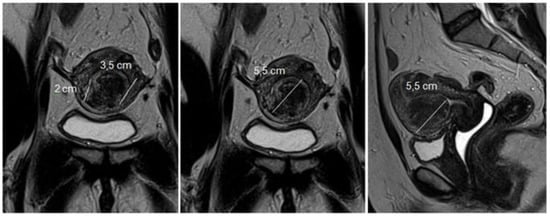

Magnetic resonance imaging of the pelvis (MRI) is indicated in uteri with a volume greater than 375 cm3 or with more than four fibroids [20]. With excellent definition regarding the number, location, size of nodules, and proximity to other myomas, it is used to diagnose adenomyosis and adenomyoma, rule out non-fibroids and sarcomas, and to measure the myometrial mantle. The myometrial mantle refers to the distance between the deepest portion of the myoma in the myometrium and the serosa, being of unique importance in hysteroscopic myomectomy, since confirmation of transmural myoma (the one that reaches the serosa) contraindicates the hysteroscopic approach due to the high probability of uterine perforation during the procedure (Figure 4).

Figure 4. MRI with submucous myoma.